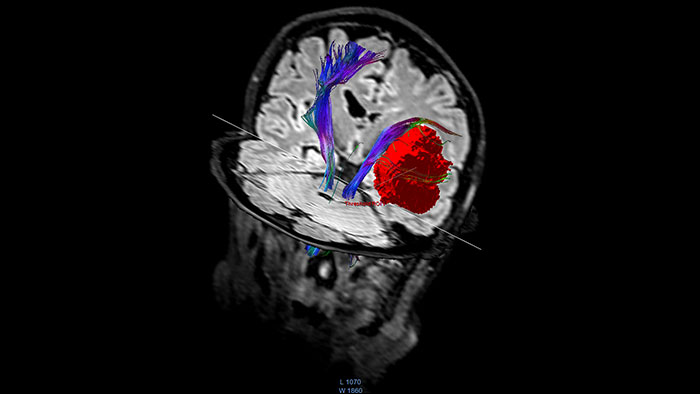

Visualize white matter connectivity in the brain

Provides visualization and quantification of white matter structure in the brain and spinal tracts using task guidance for generating common or user-defined tracts.